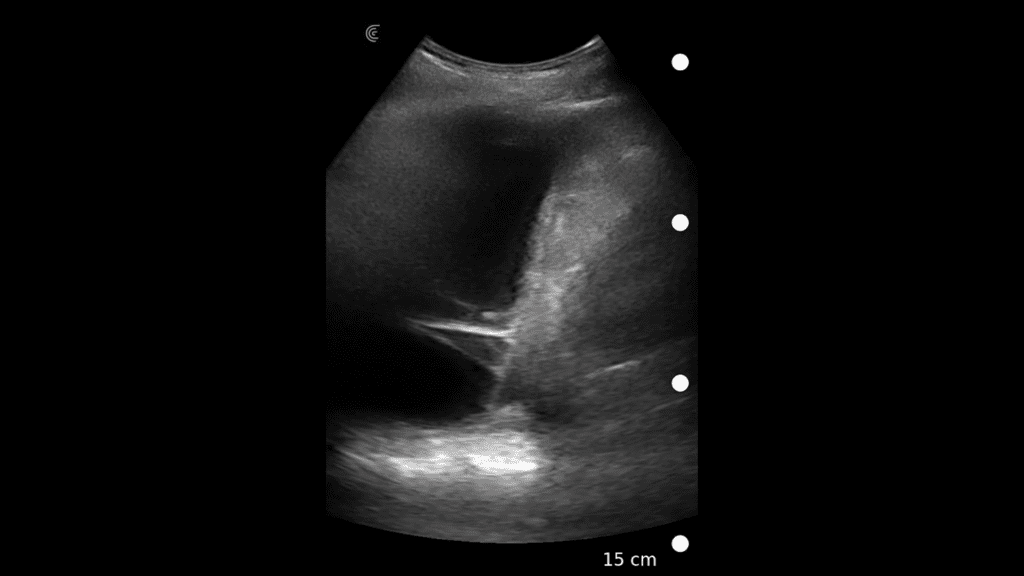

T-Mode es un enfoque innovador para la educación en ecografía diseñado para mejorar sus habilidades de escaneo utilizando la potencia de la inteligencia artificial en aplicaciones de Estética y Cirugía Plástica. Cette technologie novatrice superpose des couleurs distinctes, des motifs et des étiquettes pour identifier et différencier les structures anatomiques et les couches de tissu.